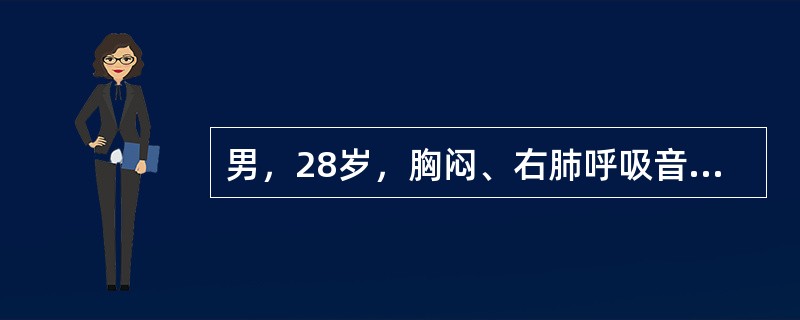

男,28岁,胸闷、右肺呼吸音减弱,请结合影像图像,选择最可能的诊断()

A.畸胎瘤

B.胸腺瘤

C.肺癌

D.先天性囊性腺瘤样畸形

E.支气管囊肿

[单选题]男,28岁,胸闷、右肺呼吸音减弱,请结合影像图像,选择最可能的诊断()A .畸胎瘤B .胸腺瘤C .肺癌D .先天性囊性腺瘤样畸形E .支气管囊肿